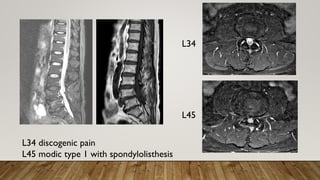

L34

L45

L34 discogenic pain

L45 modic type 1 with spondylolisthesis

right L34 discography

right L45 discography with epidural spreading

PAIN SCORE

• Pre interventionVAS 3

• back pain improved toVAS 2 after 1

week

• Able to walk for 1 hour after 1week